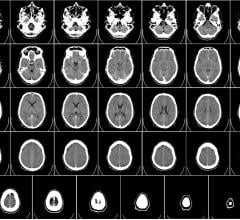

April 26, 2016 — Repeated head impacts to high school football players cause measurable changes in their brains, even ...